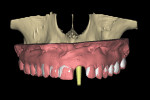

Recent software developments allow for a simulated implant to be visualized in the axial view in close proximity to the incisal canal (yellow arrow), and the periodontal ligament space of the adjacent tooth roots (Figure 5). Using advanced software features and the process of segmentation, the existing tooth root can be virtually extracted, leaving the remaining alveolus to be inspected (Figure 6). The use of “selective transparency” provides the necessary information regarding positioning the implant and avoiding the adjacent tooth roots (Figure 7). The proposed implant with an abutment projection can then be positioned to emerge through the desired restorative result, linking the implant to the envelope of the tooth.

Utilization of a digitized diagnostic wax-up or duplicate of a patient’s denture scanning appliance provides an unparalleled ability to visualize the relationship between the desired tooth and the underlying bone. The virtual implant can then be positioned within the receptor site to fit within the envelope of the desired restoration. It is essential to place a virtual abutment or an abutment “projection” with an appropriate vertical height to visualize the spatial positioning of the abutment as it relates to the tooth to achieve restoratively driven outcomes (Figure 8). Once the implant position has been finalized, a surgical guide can then be fabricated, facilitating proper implant placement (Figure 9). Precise and accurate templates can be fabricated by either CAD/CAM or 3D printing technologies, which are becoming much more affordable for both dental laboratories and clinicians.